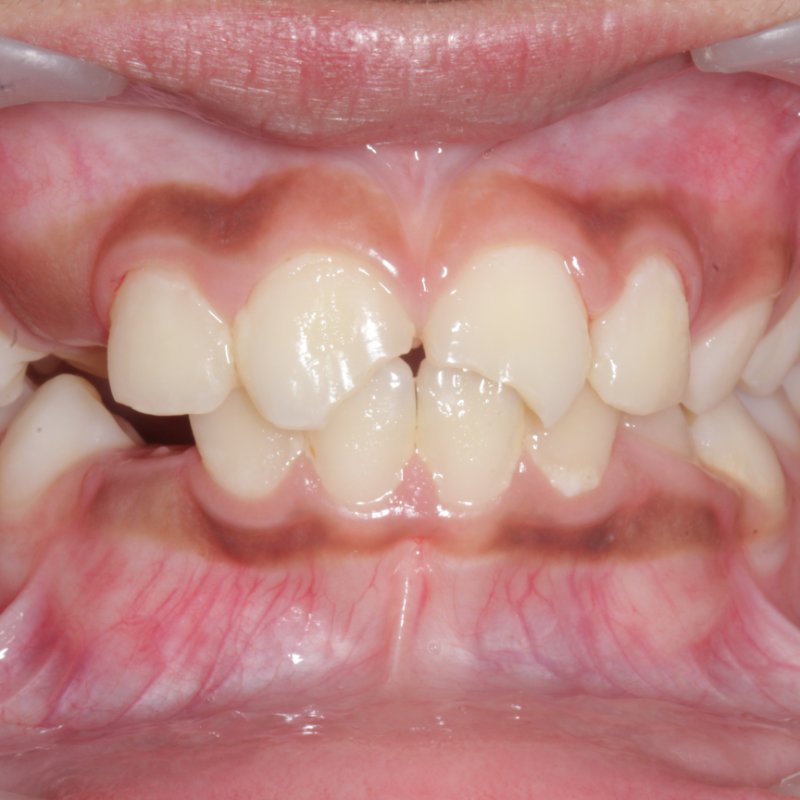

Before invisalign treatment

Invisalign

Clear aligner orthodontics

Crowding and a midline gap corrected with a series of clear aligners — no metal brackets, fully removable for daily life.